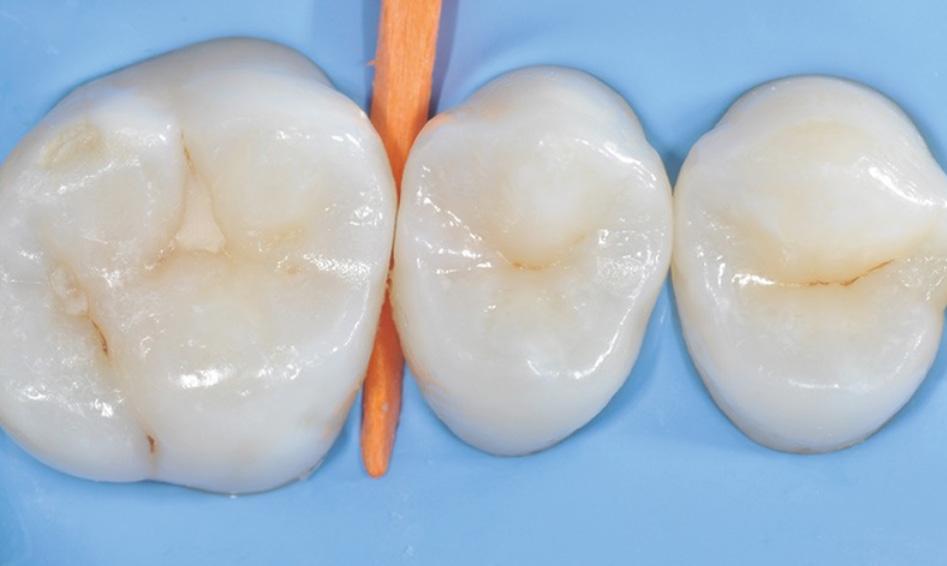

Fig. 1: Radiograph of initial situation: second upper premolar with deep carious lesion close to pulp. Fig. 2: Preop: intact occlusal surface of the second premolar, carious lesion was visible on radiograph. Fig. 3: Insertion of a proximal wedge. Fig. 4: Customization of sectional matrix clamp.

Fig. 5: Caries removal and cavity preparation. Caries detection dye was used as a Fig. 6: A 15 second selective enamel etch using 3M™ Scotchbond™ Universal Etchant followed by rinsing and air drying. Fig. 7: 3M™ Scotchbond™ Universal Adhesive was scrubbed into the preparation for 20 seconds followed by air-drying and light-curing with 3M™ Elipar™ LED Curing Light for 10 seconds.* Fig. 8: 3M™ Filtek™ One Bulk Fill Restorative A3 was placed in one increment. The composite was cured for 10 seconds on the occlusal surface.*